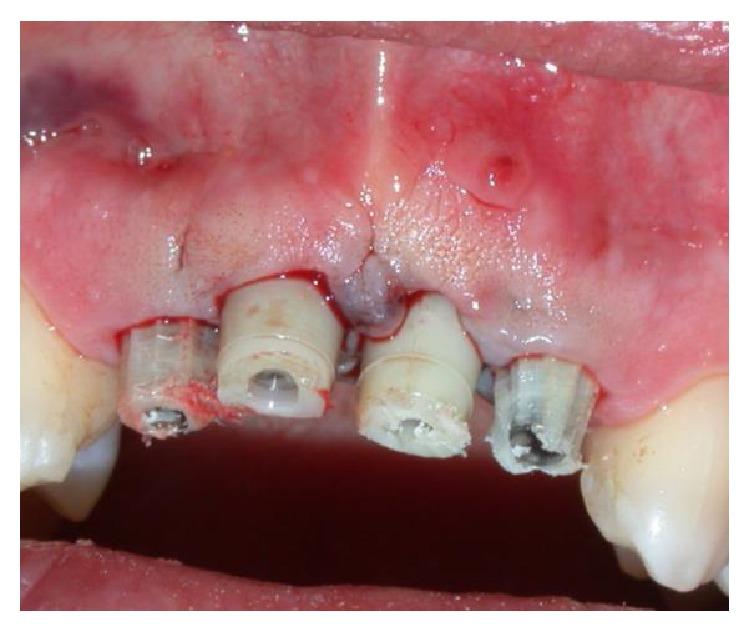

The functional and aesthetic restoration of teeth compromised due to aggressive periodontitis presents numerous challenges for the clinician. Horizontal bone loss and soft tissue destruction resulting from periodontitis can impede implant placement and the regeneration of an aesthetically pleasing gingival smile line, often requiring bone augmentation and mucogingival surgery, respectively. Conservative approaches to the treatment of aggressive periodontitis (i.e., treatments that use minimally invasive tools and techniques) have been purported to yield positive outcomes. Here, we report on the treatment and five-year follow-up of patient suffering from aggressive periodontitis using a minimally invasive surgical technique and implant system. By using the methods described herein, we were able to achieve the immediate aesthetic and functional restoration of the maxillary incisors in a case that would otherwise require bone augmentation and extensive mucogingival surgery. This technique represents a conservative and efficacious alternative to the aesthetic and functional replacement of teeth compromised due to aggressive periodontitis.

侵袭性牙周炎导致牙齿功能和美观受损,给临床医生带来诸多挑战。牙周炎引起的水平骨吸收和软组织破坏会妨碍种植体植入以及美观的牙龈微笑线的再生,通常分别需要进行骨增量和膜龈手术。据称,侵袭性牙周炎的保守治疗方法(即使用微创工具和技术的治疗方法)能产生积极效果。在此,我们报告了一名侵袭性牙周炎患者采用微创外科技术和种植系统的治疗及五年随访情况。通过使用本文所述方法,在原本需要骨增量和广泛膜龈手术的病例中,我们成功实现了上颌切牙的即刻美观和功能恢复。该技术是侵袭性牙周炎导致牙齿功能和美观受损时,一种保守且有效的替代治疗方法。